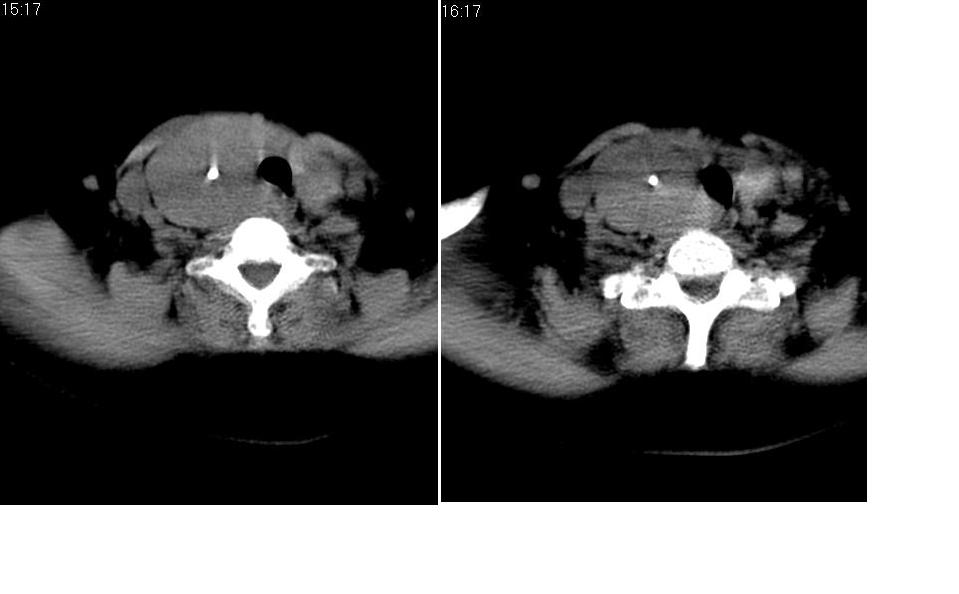

女 55岁 右侧颈部包块十年余,自己感觉有增大。

来源于右侧甲状腺  边界清晰,内可见点状钙化,向下生长达前上纵隔血管间隙内  考虑甲状腺腺瘤并胸内甲状腺肿

如果是甲状腺来源的话,那么左侧甲状腺在哪里呢?